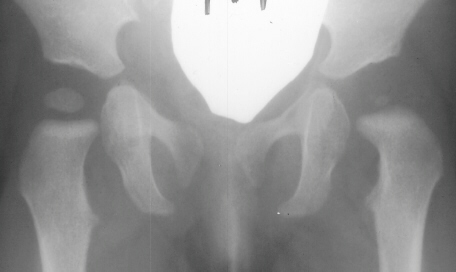

Four months later, the spica cast was removed and an Atlanta brace was applied. X-rays showed avascular necrosis at ten months of age . At two years of age, the ossification of the left nucleus was still delayed. The leg lengths were equal and the range of motion of the hip was full.

The progression of the hip is documented by x-rays taken at 1 year of age, 2 years of age, 3 years of

age, 5 years of age, 7 years of age, then at ten years of age, early closure of the lateral portion of proximal growth plate observed. Coxa valga was also observed.